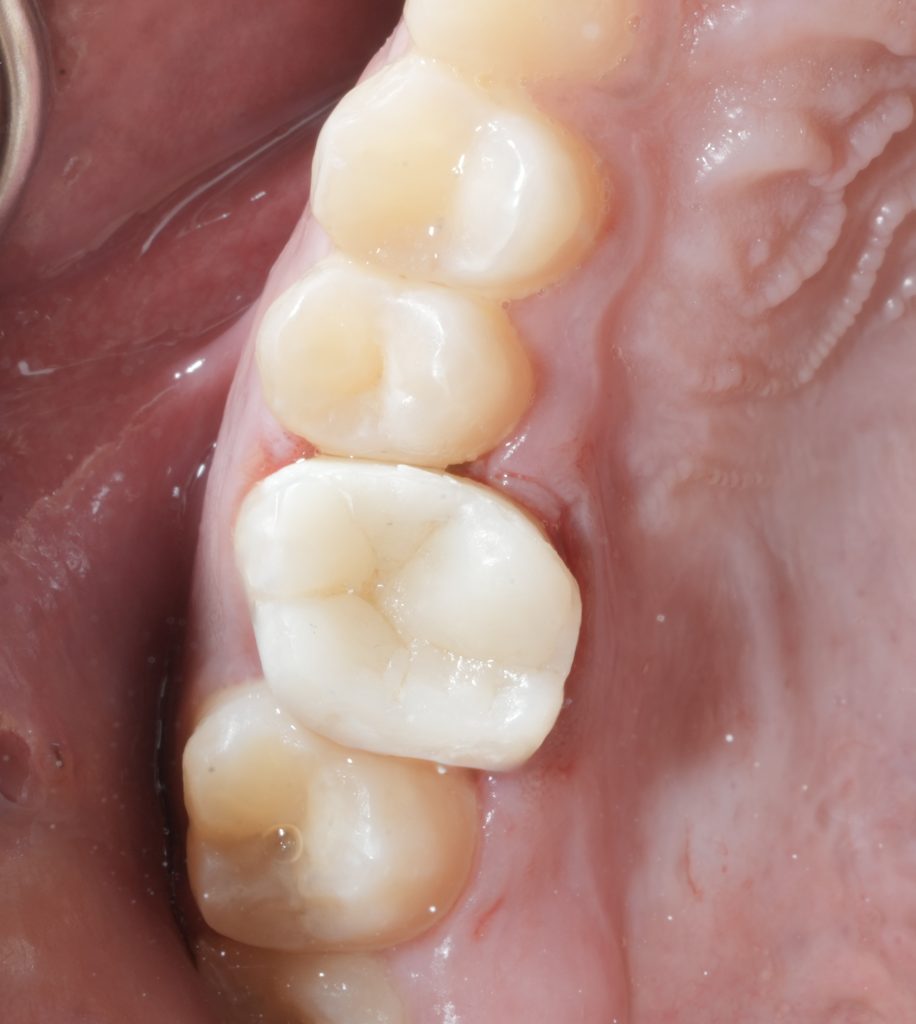

8. FINAL OUTCOME

The result shows:

- Restored biomechanics

- High aesthetics

- Smooth contours that support gingival health

- Stable occlusion with minimal material thickness

The combination of:

Endodontic cleaning + strong adhesive core + DME + composite onlay

gives the tooth a second life with maximum preservation of natural structure.